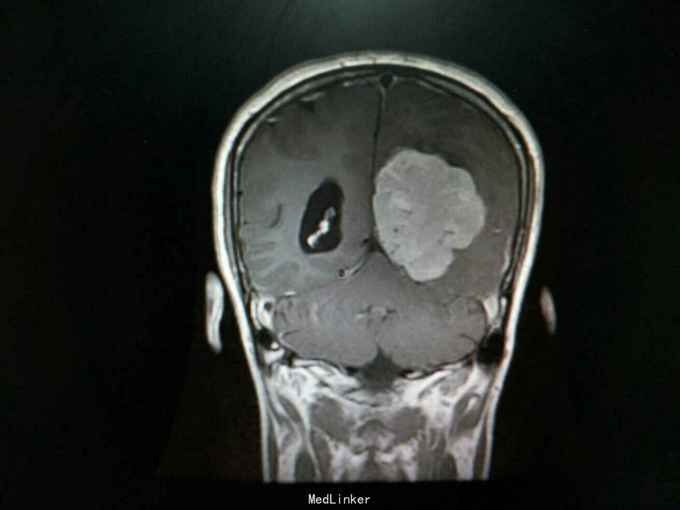

查体:生命体征平稳,神经系统检查未见明显异常。辅助检查:头颅增强+血管MR扫描提示:双侧额顶叶、侧脑室周围见斑片状异常信号区,T1WI呈等信号,T2WI及T2-FLAIR呈稍高信号。左侧枕部大脑镰旁可见团状软组织肿块影,边界清,形态不规则,呈分叶状,大小约62mm×49mm。病灶T1WI呈等信号,T2WI呈稍低信号,周围可见脑脊液环绕;增强扫描病灶明显均匀强化。病灶占位效应较明显,左侧顶枕叶脑实质受压向内移位,左侧侧脑室受压变形。中线结构稍向右移位。余脑实质未见异常信号灶。颅骨未见明确异常。头颅MRA:病灶内可见多发迂曲血管影,可见大脑后动脉及脑膜动脉供血。双侧大脑前、中、后动脉管壁光滑,走行自然,管腔未见明显扩张或狭窄,未见动脉瘤征象。Willis环未见异常。1. 左侧枕部大脑镰旁占位性病变,考虑脑膜瘤可能性大;2. 轻度脑白质疏松;2. 头颅MRA提示病灶血供来自左侧大脑后动脉及脑膜动脉;余未见异常。

诊断:左枕部大脑镰旁脑膜瘤 处理:左枕部开颅大脑镰旁脑膜瘤切除术

术后病理提示:(左顶枕叶肿瘤)脑膜瘤,上皮型,WHOⅠ级。大脑镰旁脑膜瘤是指位于大脑纵裂并与大脑镰相连的一类临床上常见的脑膜瘤,常突入一侧大脑半球内,有时可向双侧发展。也有少数肿瘤呈扁平型,在大脑镰内浸润性生长。肿瘤可由大脑镰脑膜动脉供血,也可由脑内动脉供血,其前部可来自眼动脉分支,后部来自枕动脉,中部可有脑膜中动脉供血。在肿瘤基底和附近的大脑镰内有多条扩张的静脉。